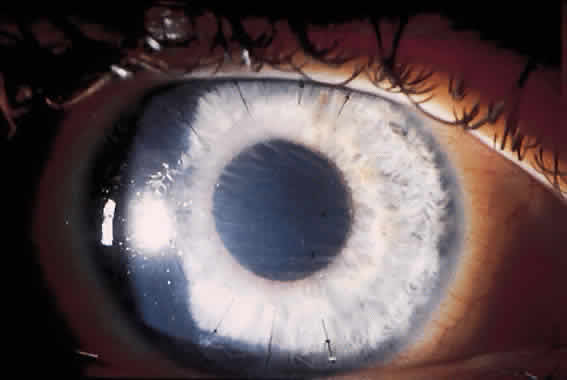

Current techniques have evolved to eliminate most of these complications. The diamond blades used today have two cutting edges. The main cutting edge is sharp for the entire length of the blade, whereas the anterior surface has a cutting surface for only 250 μm (Fig. 1). The blunt portion of the blade helps prevent inadvertent encroachment of the visual axis. Also, the new blades have a housing that will glide along the corneal surface to help keep the incisions perpendicular.

|